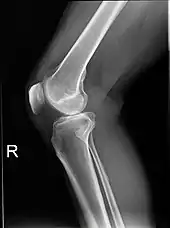

Projectional radiographs

Projectional radiography is the practice of producing two-dimensional images using X-ray radiation. Bones contain a high concentration of calcium, which, due to its relatively high atomic number, absorbs X-rays efficiently. This reduces the amount of X-rays reaching the detector in the shadow of the bones, making them clearly visible on the radiograph. The lungs and trapped gas also show up clearly because of lower absorption compared to tissue, while differences between tissue types are harder to see.

Projectional radiographs are useful in the detection of pathology of the skeletal system as well as for detecting some disease processes in soft tissue. Some notable examples are the very common chest X-ray, which can be used to identify lung diseases such as pneumonia, lung cancer, or pulmonary edema, and the abdominal x-ray, which can detect bowel (or intestinal) obstruction, free air (from visceral perforations), and free fluid (in ascites). X-rays may also be used to detect pathology such as gallstones (which are rarely radiopaque) or kidney stones which are often (but not always) visible. Traditional plain X-rays are less useful in the imaging of soft tissues such as the brain or muscle. One area where projectional radiographs are used extensively is in evaluating how an orthopedic implant, such as a knee, hip or shoulder replacement, is situated in the body with respect to the surrounding bone. This can be assessed in two dimensions from plain radiographs, or it can be assessed in three dimensions if a technique called '2D to 3D registration' is used. This technique purportedly negates projection errors associated with evaluating implant position from plain radiographs.[101]